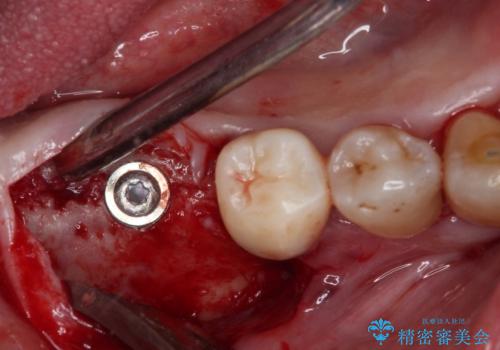

- インプラント治療を前提に下顎の部分矯正を始めたものの、そのまま長い間放置しているとのことで来院された患者様です。

矯正治療を仕上げ、必要に応じて歯周外科処置を行い、適宜インプラントを埋入しながら咬み合わせを回復させていくこととしました。

治療前は磨き残しが多く見られ、全体的に歯肉が腫れている状態でしたが、抜歯の必要な歯を抜いたことで口腔内の環境が改善され、磨き残しも少なくなってきました。

インプラントにより咬合が回復したことで、治療開始時に認められた上顎前歯の動揺も改善されました。